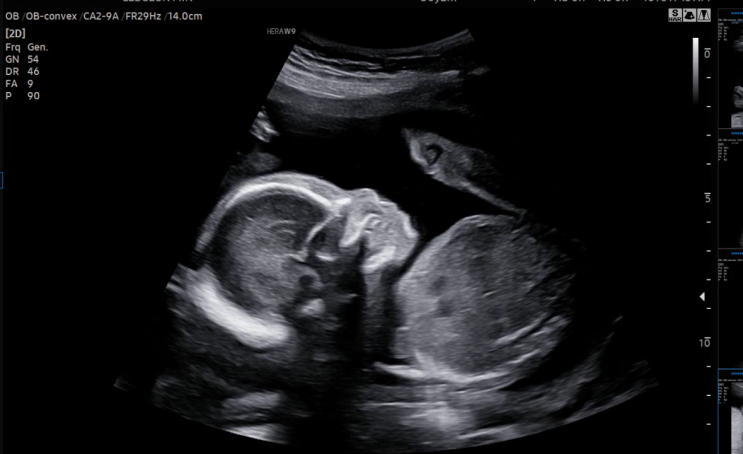

[중기] 21주~27주: 밀린 중기 기록을 끝내자..!

이번주 내내 사무실이 텅텅이라 꼭 블로그를 쓰자고 다짐했건만, 월요일부터 쓰는건 역시나 쉽지 않았네 ㅎ...